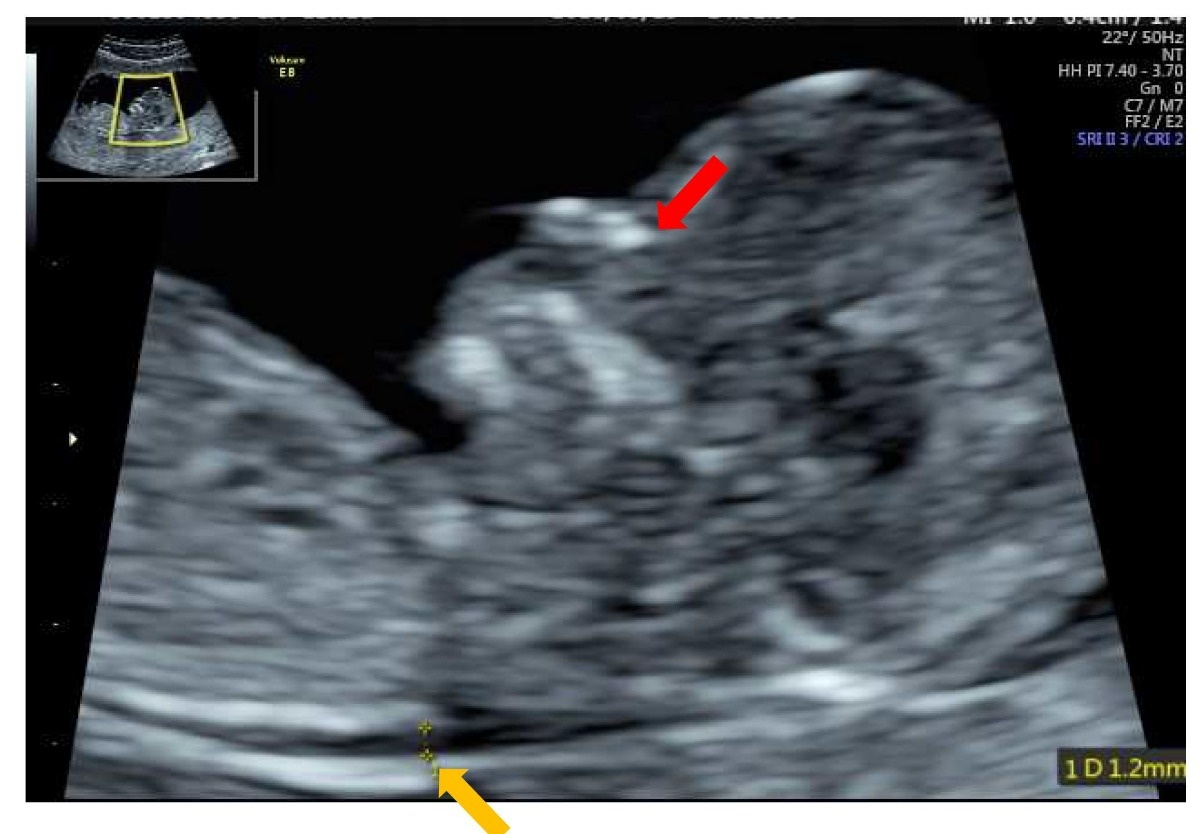

Nt エコー

先天異常部より Nt Nuchal Translucency について 医療者向け 日本産婦人科医会

Nt Nuchal Translucency ある産婦人科医のひとりごと

14 初期の超音波マーカー検査 日本産婦人科医会

先天異常部より Nt Nuchal Translucency について 医療者向け 日本産婦人科医会

02 妊娠初期 胎児の頸部浮腫 Nt 妊娠11 13週でcheck 深谷産婦人科 医学情報

胎児超音波ーマーカー検査とは ヒロクリニック

胎児の首の後ろのむくみ 浮腫 Nt とは 妊娠初期 All About

Nt Nuchal Translucency について 出生前検査 Nipt 遺伝カウンセリング 妊婦健診 エコー検査 産科 婦人科 産婦人科

胎児の首の後ろのむくみ 浮腫 Nt とは 妊娠初期 All About

胎児の首のむくみ Nt クリフム夫律子マタニティクリニック

Nt Nuchal Translucency ある産婦人科医のひとりごと

Nt Nuchal Translucency ある産婦人科医のひとりごと